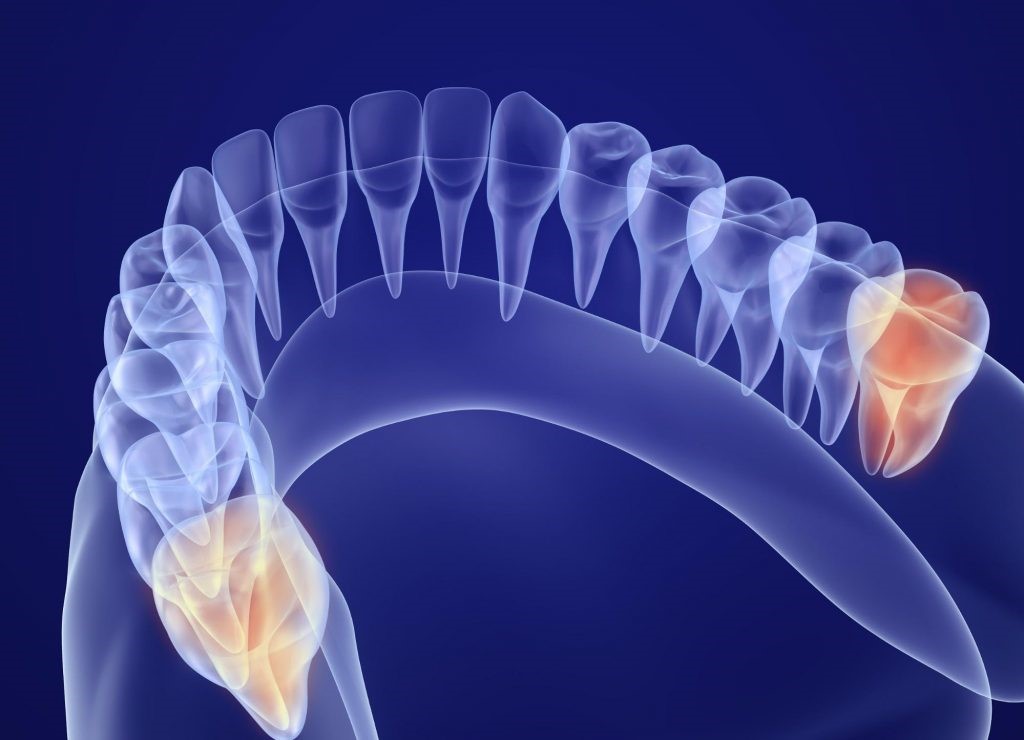

隠れたリスクも洗い出す、CTによる精密分析

親知らずの抜歯はしっかりと事前の診査診断を行わなければ血管や神経を傷つけてしまい、多量の出血や麻痺が生じる場合もあります。

特に下顎の親知らずの場合、根の先が下顎の骨の中にある下歯槽管の近くにあることが多いのですが、この下歯槽神経が傷つけられると、下唇や下顎の皮膚、口腔内粘膜や歯茎が知覚障害を起こし、会話や食事が上手にできなくなってしまうこともあります。

レントゲン写真では、親知らずの歯がどのように顎の骨に埋まっているのか、神経が親知らずと接触しているかどうかの確認が正確に行えないため、CT撮影をして親知らずの埋まり方や歯根の形、神経や血管との距離など正確に診断する必要があります。

また歯茎に埋まっている親知らずや横向きに生えている親知らずも、根の先と下顎管が近接しているケースが多いため、抜歯の際にはCT撮影による事前の綿密な診査診断がとても重要です。